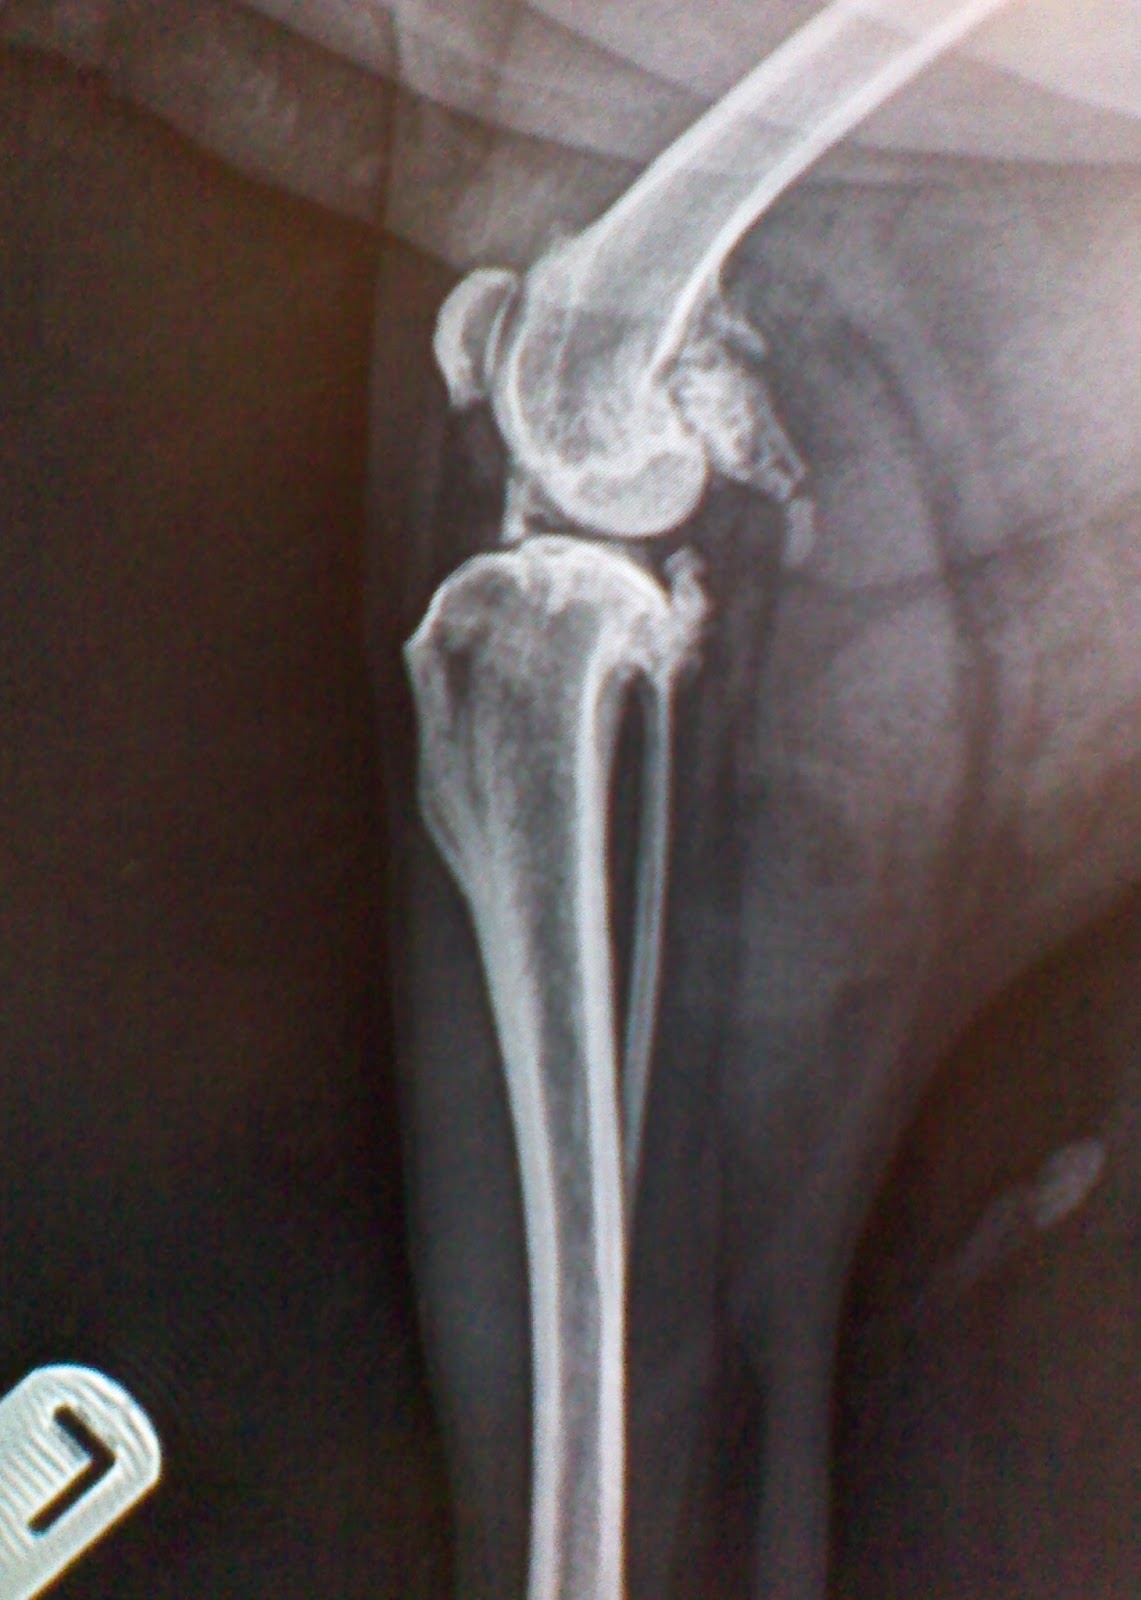

A 7yearold dog with severe and chronic septic arthritis of the Septic Arthritis Dog Vin nsaids are an important component of arthritis therapy in dogs. infective (septic) arthritis is an inflammatory arthropathy caused by an infective agent, most commonly bacteria. clinical signs of septic arthritis include lameness, swelling, pain of affected joint(s), and systemic signs of fever, malaise,. septic arthritis, degenerative arthropathies and immune mediated processes. Other differentials include degenerative, traumatic,. Septic Arthritis Dog Vin.